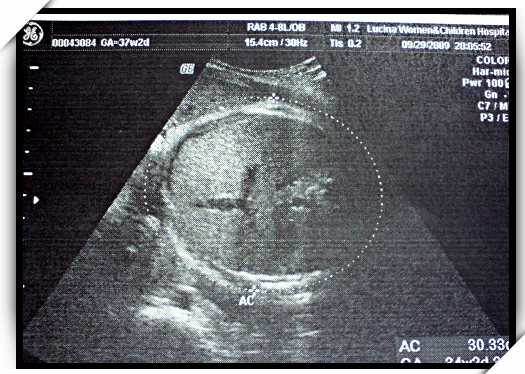

量了小石頭的肚圍好幾次 :p

(baby的重量是看頭圍+肚圍+大腿骨三個數據概算出來的)

還說,小朋友的肚子都沒有長大耶...

下圖就是小石頭的肚圍...都沒有長大...